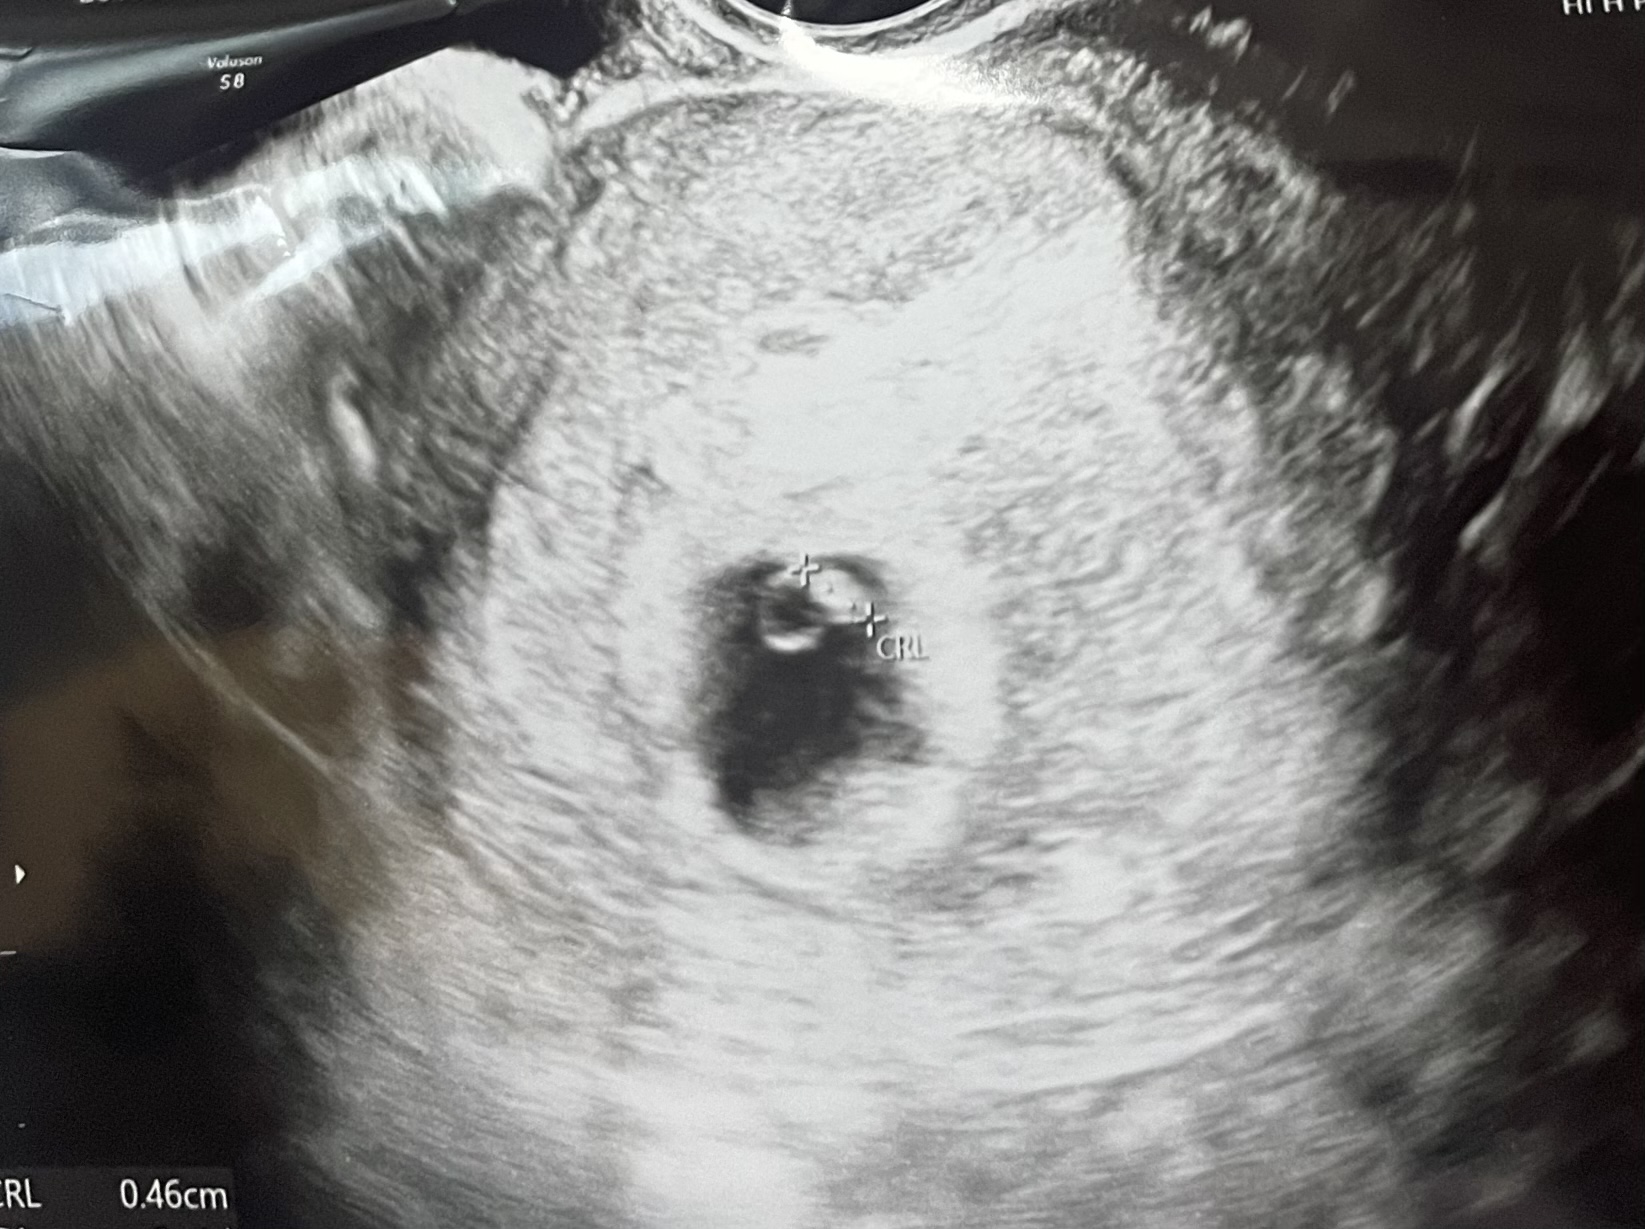

| 치료 도중 느꼈던 가장 기뻤던 순간과 절망적인 것들은 무엇인가요? 잊지 못할 경험이 있나요? | 이식 후에는 기대를 거의 하지 않았는데, 임신 테스트기에서 두 줄을 보았을 때가 가장 벅찼습니다. 반대로 인공수정에 기대를 걸었다가 단호하게 실패했을 때는 마음이 많이 무너졌던 기억이 납니다. 그래도 이후 아기집을 보고 심장소리까지 들었을 때는 말로 표현하기 어려울 만큼 감격스러웠습니다. |